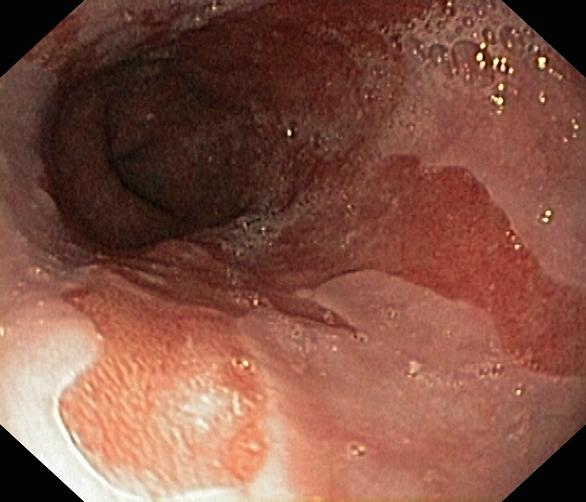

Przełyk Barretta